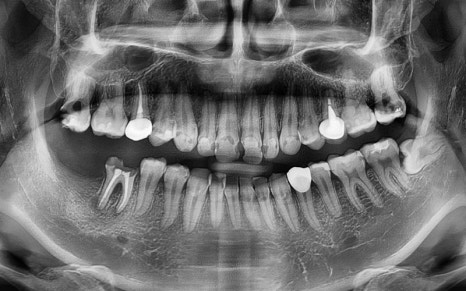

The patient we are introducing had several cavities in progress,

and the pain would come and go,

which made it even easier to miss the right timing for treatment.

As can actually be seen in the treatment record,

more than 10 teeth received

root canal treatment,

and most were accompanied by complex inflammation and nerve infection.

A panoramic X-ray was taken

to perform a detailed check,

and an overall treatment plan was established.